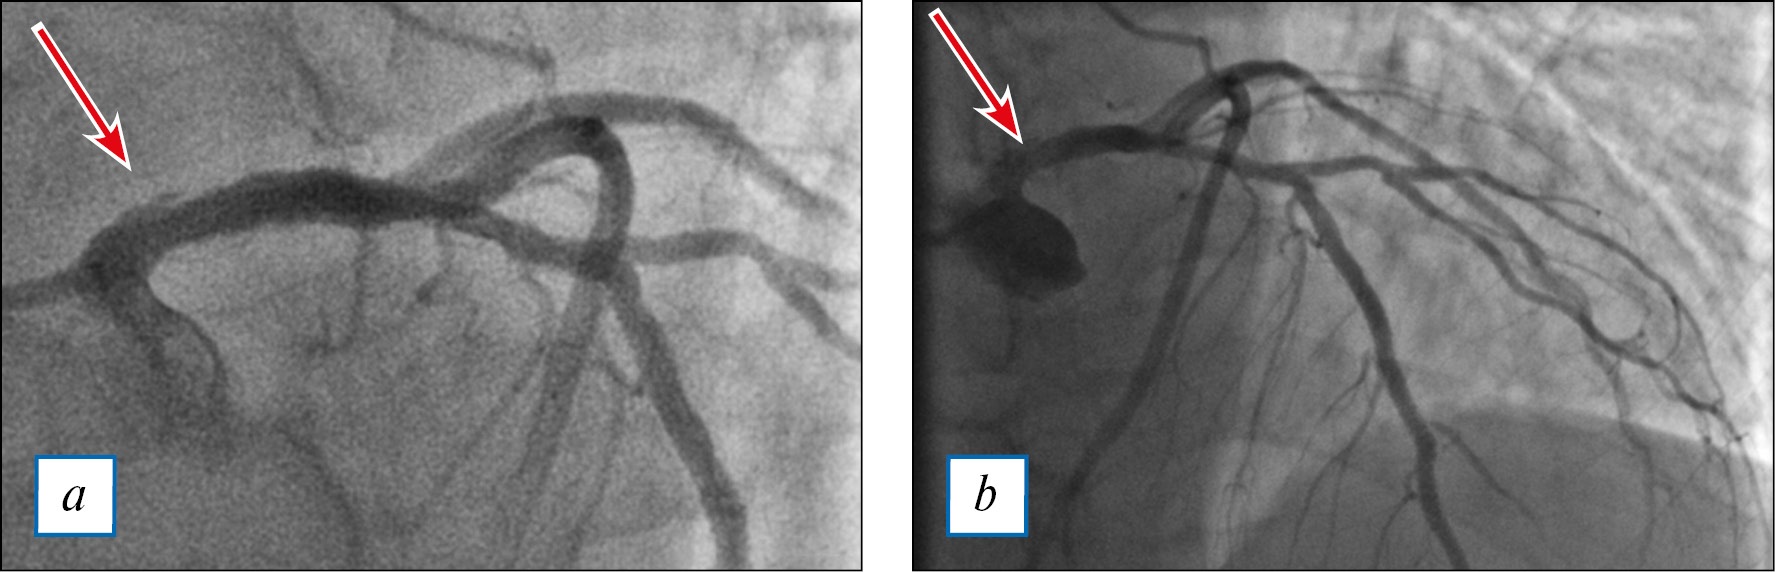

По данным селективной коронарографии визуализируется расслоение ствола левой коронарной артерии (рис. 3, a), остальной бассейн левой коронарной артерии без гемодинамически значимых поражений (рис. 3, b); правая коронарная артерия без особенностей (рис. 4). Левый тип кровоснабжения миокарда.

Рис. 3. Тот же пациент: селективная коронарография левой коронарной артерии.

Примечание. a — увеличенное изображение (расслоение ствола левой коронарной артерии отмечено стрелкой); b — передняя нисходящая, огибающая, диагональная артерии и ветвь тупого края без гемодинамически значимых поражений (стрелкой отмечено расслоение ствола левой коронарной артерии).

Fig. 3. The same patient: selective coronary angiography of the left coronary artery.

Note. a — enlarged image (dissection of the trunk of the left coronary artery is marked with an arrow); b — left anterior descending, circumflex, diagonal arteries and obtuse marginal branch without a hemodynamically significant damage (dissection of the trunk of the left coronary artery is marked with an arrow)

С учетом высокой вероятности распространения диссекции на переднюю нисходящую и огибающую артерии, при наличии острейшего повреждения миокарда и необходимости выполнения хирургического лечения на восходящем отделе аорты принято решение об имплантации голометаллического стента в ствол левой коронарной артерии.

Выполнена успешная имплантация стента «Синус» (НПК «Ангиолайн», Россия) диаметром 5 мм и длиной 12 мм в ствол левой коронарной артерии (рис. 5).

Рис. 5. Тот же пациент: результат стентирования ствола левой коронарной артерии.

Fig. 5. The same patient: results of the left coronary artery stenting.